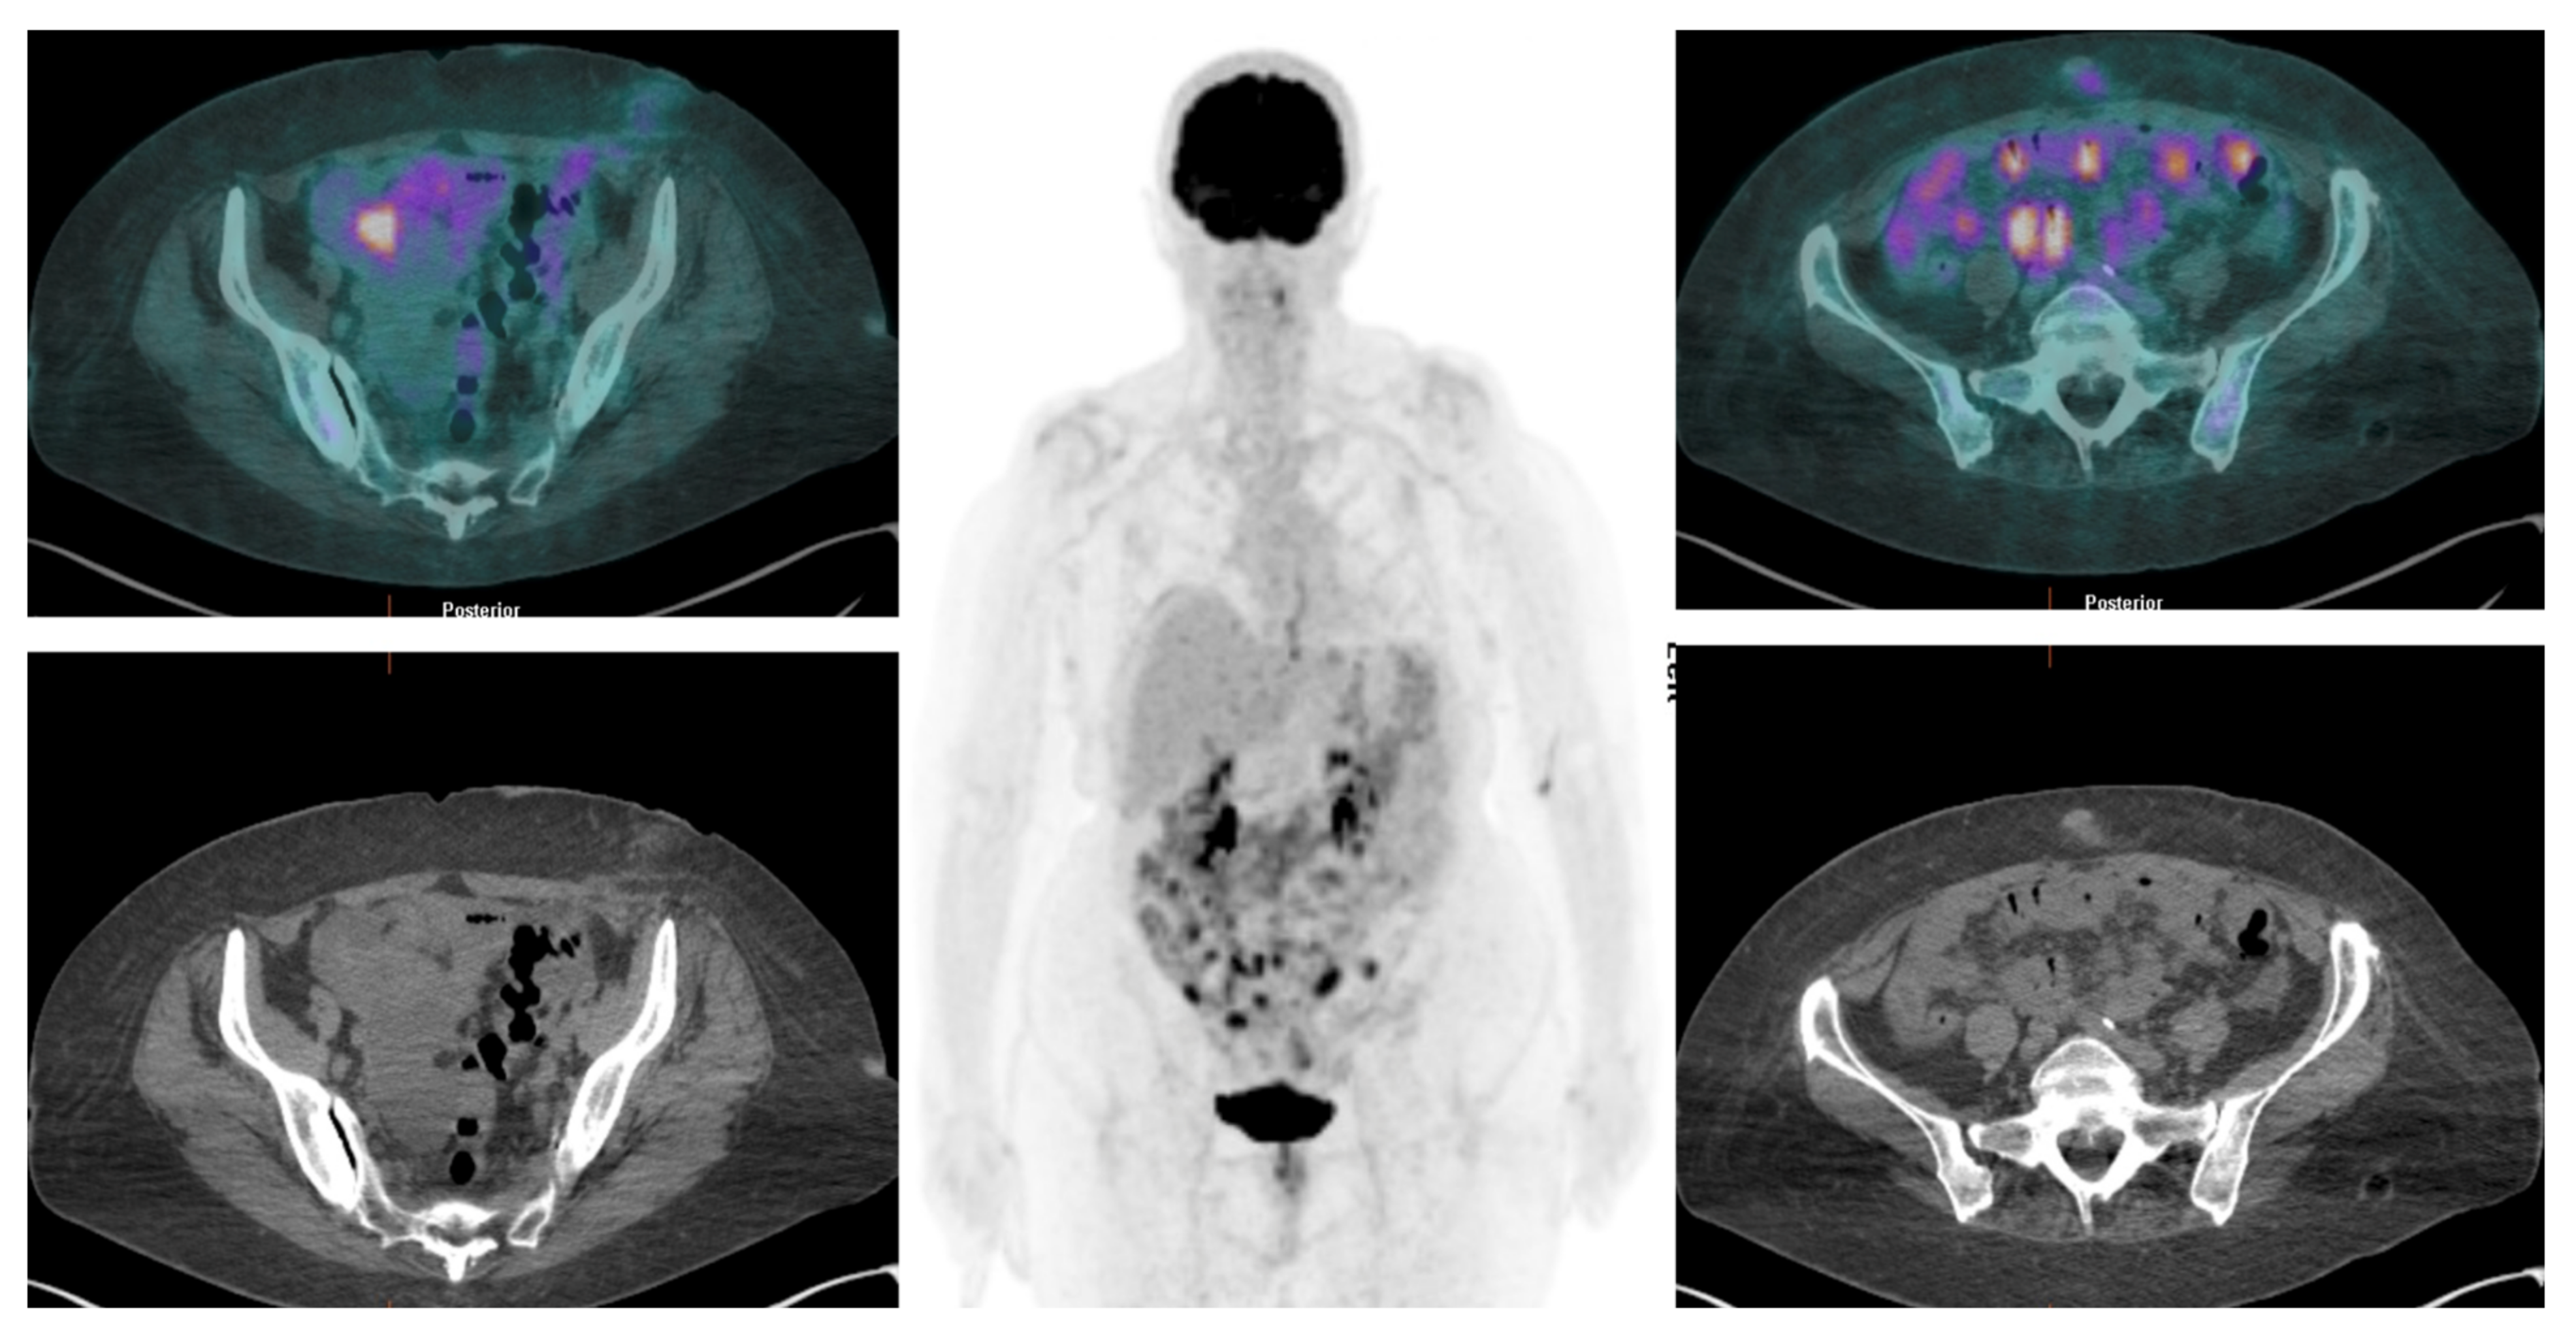

Over the past decade, numerous studies have highlighted the ability of [18F]FDG PET/CT over CT in detecting lymphadenopathies and peritoneal distant metastases associated with solid tumors (Figure 5 and Figure 6).

Figure 6. [18F]FDG PET/CT detects multiple nodular hypermetabolic lesions in the abdominopelvic region, suggestive of peritoneal carcinomatosis.